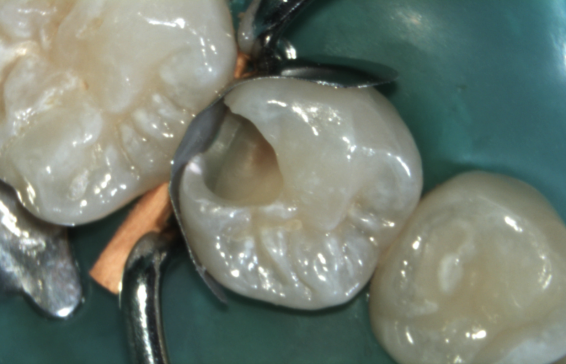

Vorbereitung der Zahnsubstanz für den haltbaren Haftverbund

Auftragen von Haftvermittlern (3 Schritte)

Schichten der Komposit-Keramik

Modellation, Ausarbeitung & Politur

Fertig: Die ästhetische Kompositfüllung!